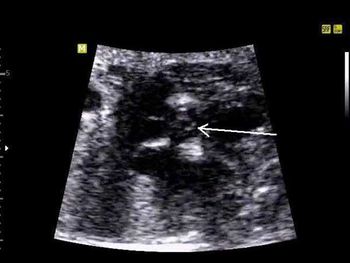

A routine ultrasound exam of a 28-week fetus revealed what looked to be a cystic lesion. The addition of Doppler, however, changed the diagnostic picture.